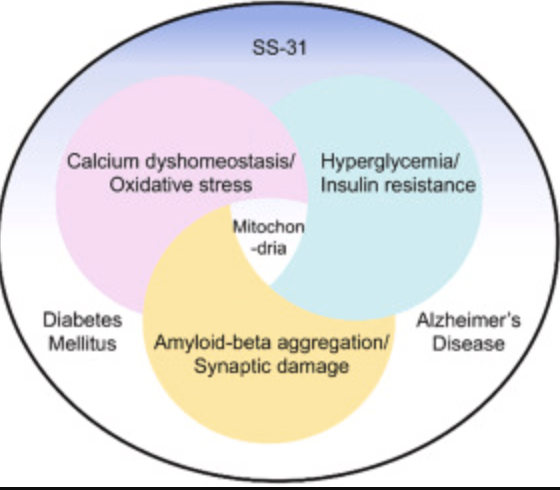

SS-31 & Renal Fibrosis

SS-31 is a mitochondria-targeted tetrapeptide that has gained interest for its protective effects against oxidative stress-induced tissue damage. SS-31 can repair mitochondrial dysfunction. It has antioxidant properties; therefore, it scavenges reactive oxygen species (ROS) within mitochondria, preventing oxidative damage to renal tubular cells. SS-31 has been found to decrease the levels of pro-inflammatory cytokines and inhibit pathways involved in cellular death. Its role in targeting renal fibrosis role of SS-31 is primarily attributed to its antioxidant properties, ability to modulate inflammatory pathways, and protective effects on renal cellular structures.

Image: https://www.sciencedirect.com/science/article/abs/pii/S1043661821003674

Peptides hold promise as therapeutic agents for preventing or treating kidney fibrosis through mitochondrial protection, reducing inflammation and oxidative stress, and restoring cellular homeostasis. Peptides’ ability to address many of the pathological mechanisms makes them suited to the complex, self-perpetuating cycles of kidney fibrosis.